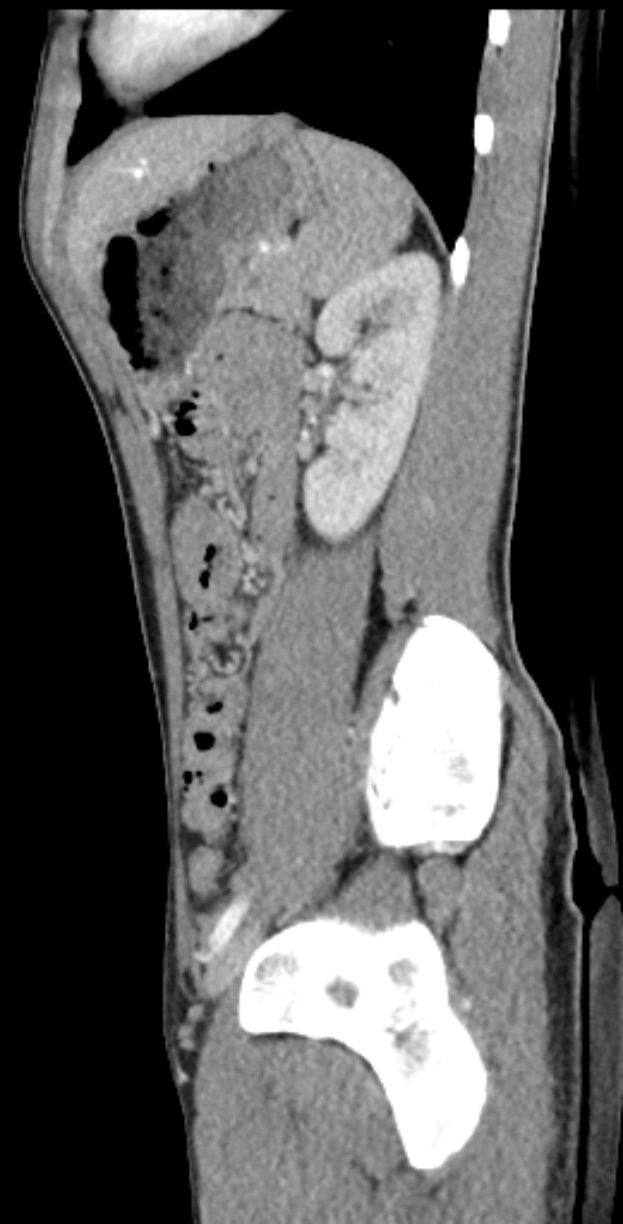

Eine MRT-Aufnahme eines Knies, die einen Bruch in der Mitte zeigt, umgeben von einem dunklen Hintergrund.Hiltrud Bolnbach

Muskelverletzungen: Köln vorerst ohne Thielmann und Sebulonsen - Doppelschlag für den 1. FC Köln: Zwei Schlüsselspieler fallen gleichzeitig aus

Der 1. FC Köln muss einen herben Dämpfer hinnehmen: Gleich zwei Schlüsselspieler zogen sich im Bundesliga-Spiel gegen Hoffenheim Muskelverletzungen zu. Sowohl Jan Thielmann als auch Sebastian Sebulonsen mussten während der Partie verletzungsbedingt ausgewechselt werden. Ihr Ausfall wirft Fragen für die anstehenden Spiele des Teams auf.